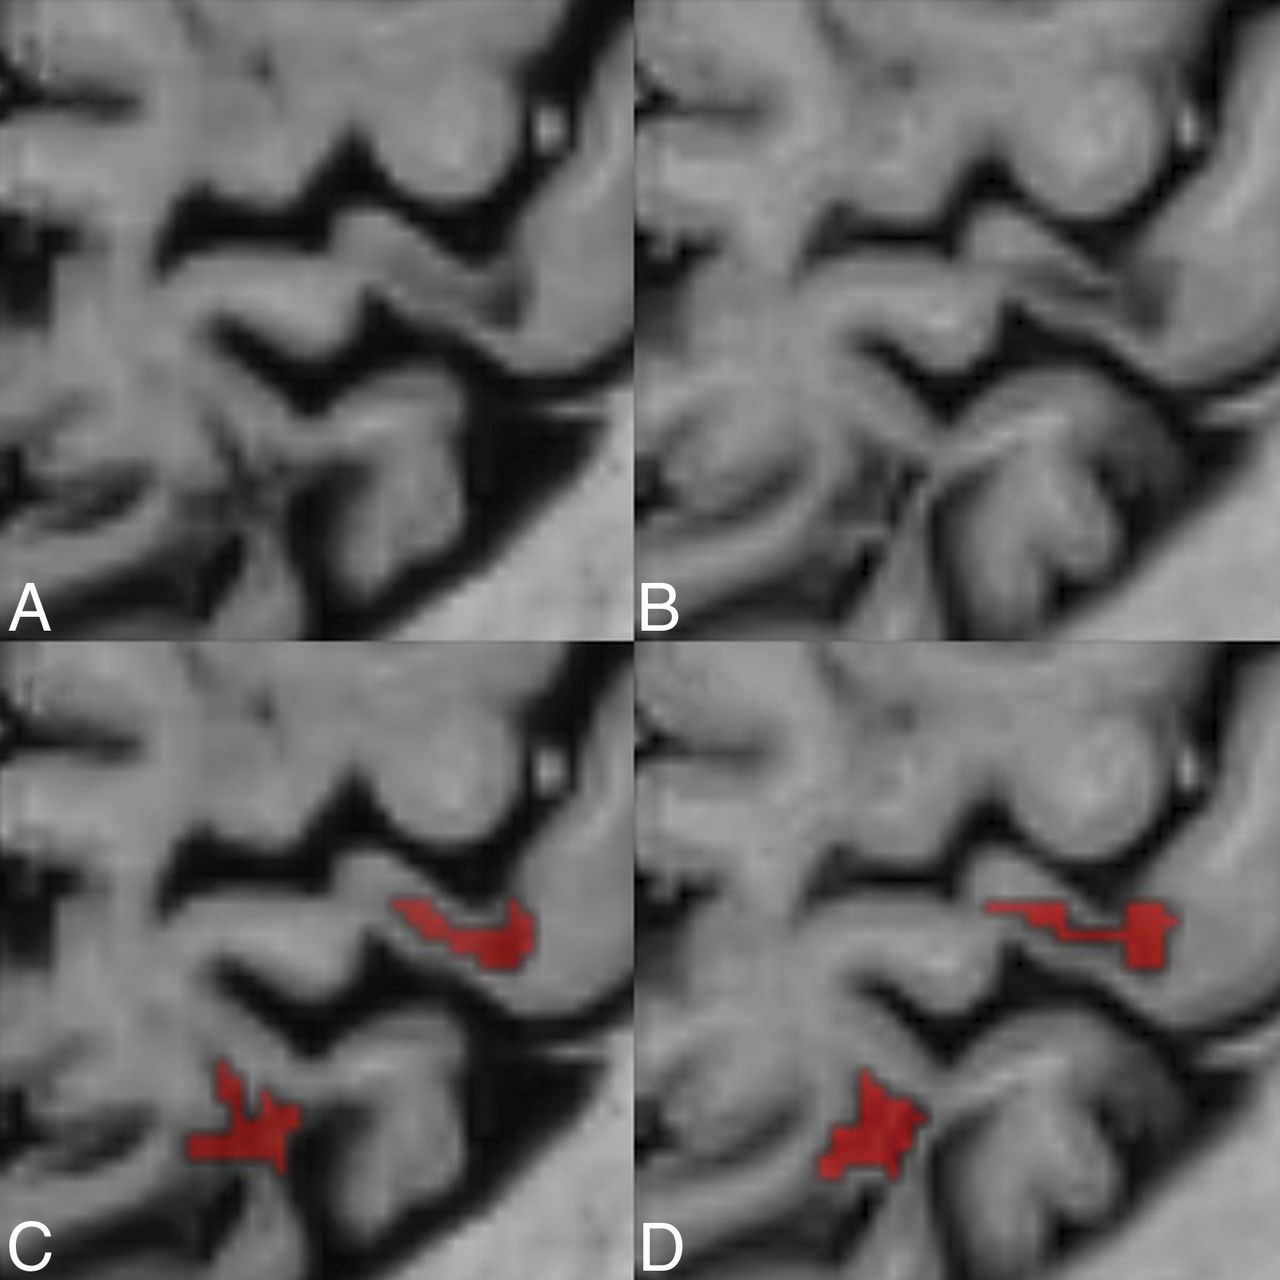

The ICC between the 2 raters was excellent for LCL for both conventional PSIR (0.79, P < .001) and synthetic PSIR (0.87, P < .001). Both raters also had excellent agreement with the consensus rating on both conventional (ICC = 0.91 and 0.97, respectively, for each rater, P < .001) and synthetic PSIR (ICC = 0.92 and 0.94, P < .001). There was no significant difference in the number of detected LCL between conventional and synthetic PSIR (P = .47 and P = .08, respectively, for each rater). Figure 1 illustrates the relation of the individual lesion ratings and the consensus rating as well as the relation between conventional and synthetic PSIR. The 2 raters seemed to have relatively larger differences in their LCL counts in patients with fewer lesions. When we compared each individual rating with the consensus rating, one of the raters showed a small-but-significant difference between the individual and consensus rating in the LCL count on conventional PSIR (P = .008, by the Wilcoxon signed rank test). There was no significant difference between the manually segmented LCL volumes on conventional and synthetic PSIR (P = .17). A detailed comparison of the lesion counts and volumes is presented in Table 3. Figure 2 illustrates the appearance of 2 leukocortical lesions on conventional and synthetic PSIR.

Comparison between conventional and synthetic phase-sensitive inversion recovery. A comparison between conventional (B and D) and synthetic phase-sensitive inversion recovery (A and C) illustrates 2 leukocortical MS lesions in a 40-year-old female patient with MS. Lower row illustrates the manual segmentation of the lesions by a neuroradiologist.